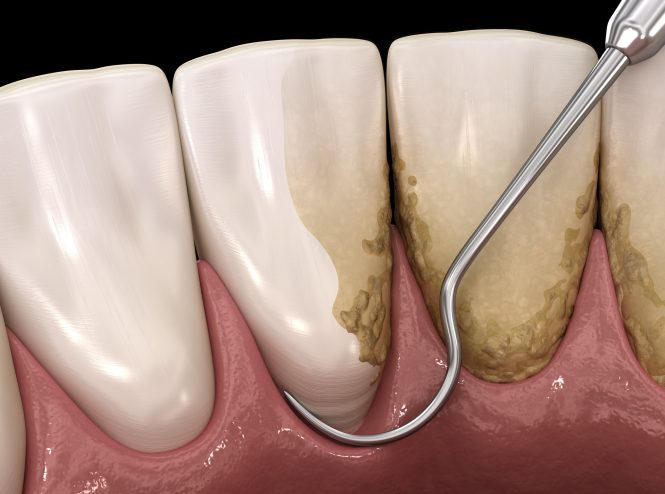

جرمگیری دندان چیست؟ چگونه انجام میشود مزایا و معایب جرمگیری دندان (Scaling) یکی از روشهای درمانی در زمینه…